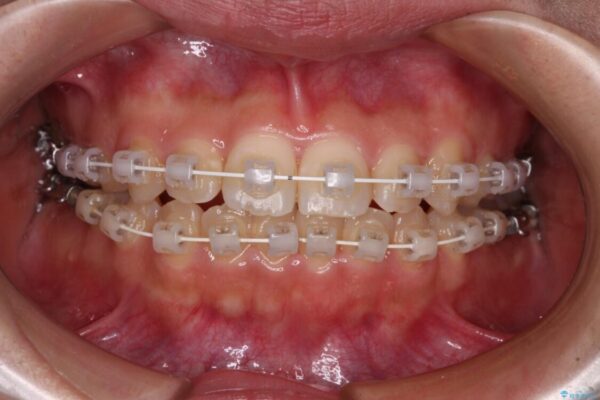

治療後

• 【モニター】短期間で終わりたい ワイヤー装置での非抜歯矯正 治療後画像

当初予定通り、1年で治療を終えることができました。